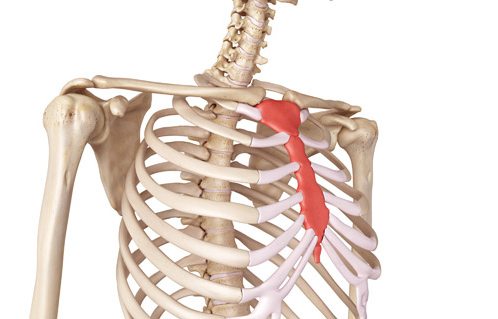

腎経で重要な気門の場所は胸骨周囲がポイントです。イメージとしては、この場所に穴を開けるようにと意識しながらおこなうことで、気門が開きやすくなり、次に経穴を治療するときにより効果を発揮します。

肝経の気門で剣状突起周辺を開いていきます。イメージとしては、この場所に穴を開けるようにと意識しながらおこなうことで、気門が開きやすくなり、次に経穴を治療するときにより効果を発揮します。